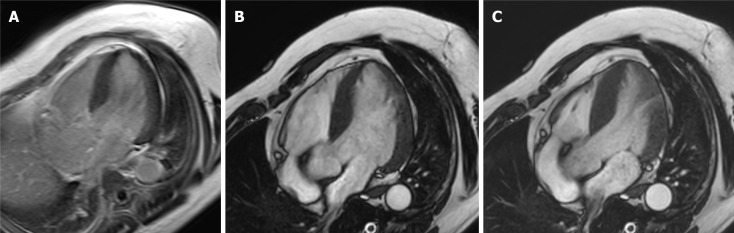

Results: Among 19 patients experiencing OHCA, 7 experienced it in trains or on railway platforms, 4 while practicing sports, and 4 during their daily work. Ten of the 19 survivors were diagnosed with coronary vasospasm (CVS), in whom CMR failed to depict its characteristic findings. CMR was useful for identifying myocardial damage associated with hypertrophic cardiomyopathy (HCM) or myocardial infarction (MI). LGE was related to serious ventricular arrhythmias after implantable cardioverter defibrillator (ICD) installation in 3 patients (CVS, 2; HCM, 1).

Conclusion: CMR is useful for identifying myocardial damage of HCM or MI inducing OHCA and predicting ventricular arrhythmias after ICD implantation but has limited capability for detecting myocardial damage of CVS.